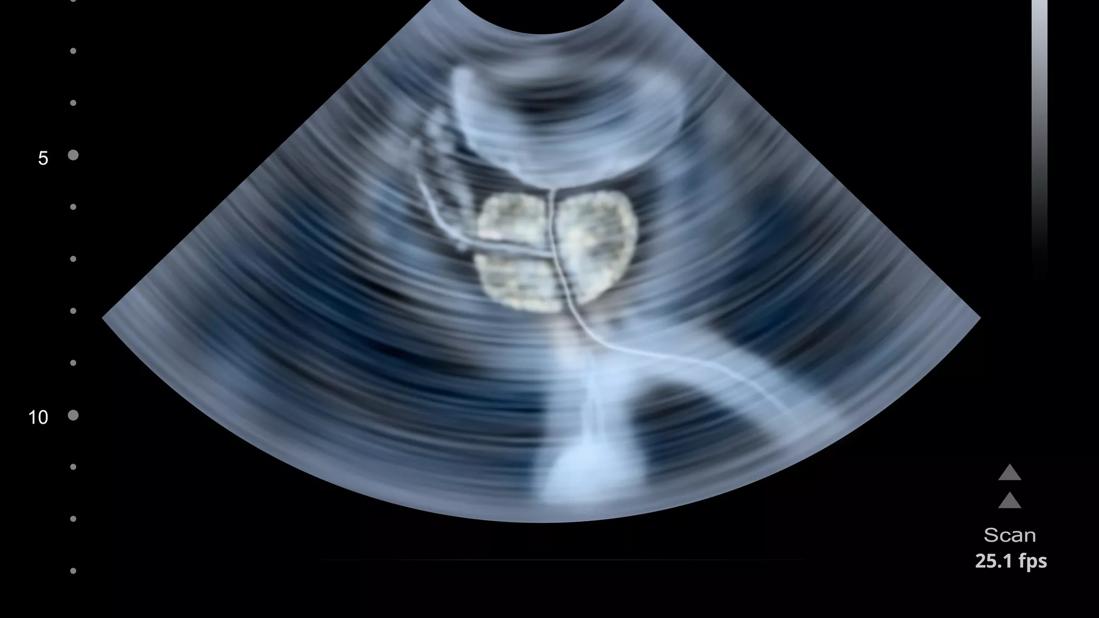

Transperineal ultrasound a viable, non-invasive option for monitoring intra-fractional prostate motion

Prostate ultrasound

Research led by a team of Cleveland Clinic experts demonstrates the feasibility and clinical efficiency of ultrasound-guided prostate stereotactic body radiation therapy using a 4D transperineal ultrasound system.

In this prospective study, Dr. Guo and her colleagues highlight their clinical experience using a transperineal ultrasound system as a means to monitor intra-fractional prostate motion for prostate stereotactic body radiotherapy (SBRT).

Data confirmed that the ultrasound image quality was sufficient for visualization of the prostate and surrounding organs at risk. The setup time for each fraction under ultrasound-guided prostate SBRT was 15.0 ± 4.9 minutes. The total treatment time per fraction was 31.8 ± 10.5 minutes.